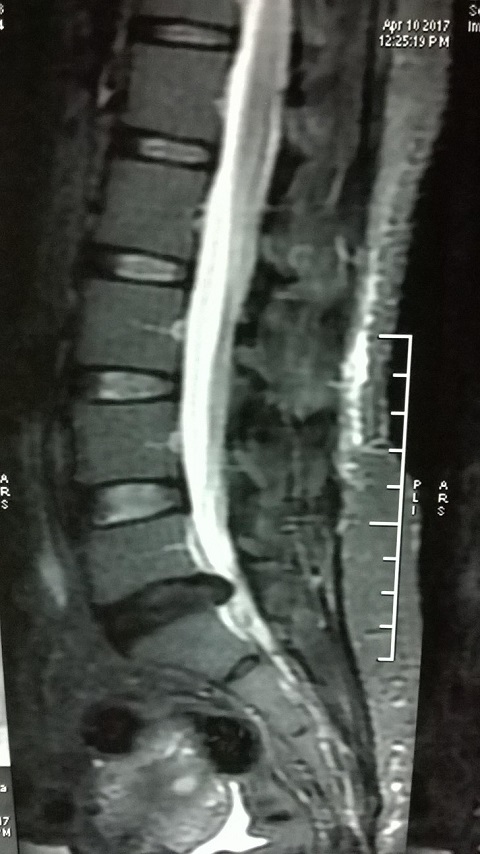

MRI of Gouri Shankar Mohapatra